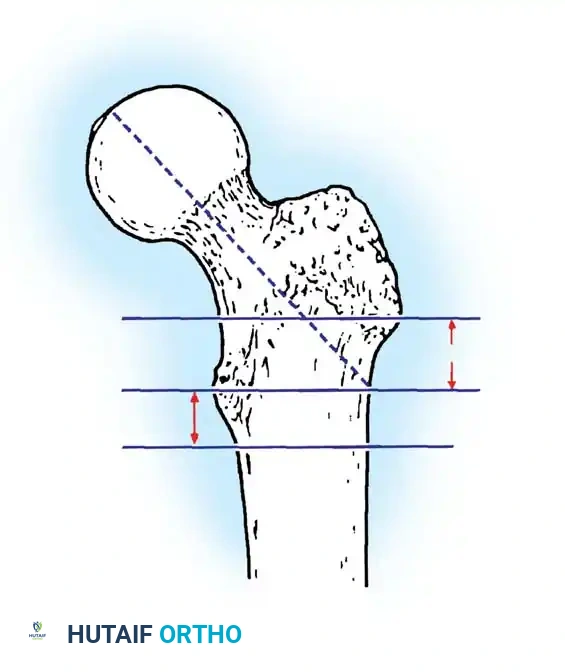

The patient is placed supine on a radiolucent fracture table. The operative leg is secured in a traction boot, and the well leg is placed in a hemilithotomy position or scissored posteriorly to allow unobstructed access for the C-arm fluoroscope.

Proper patient positioning on the fracture table is paramount. Ensure the C-arm can freely rotate from AP to lateral without obstruction.

Closed Reduction Maneuver:

1. Apply longitudinal traction to restore leg length.

2. Internally rotate the leg (typically 10 to 15 degrees) to correct the external rotation deformity and bring the femoral neck parallel to the floor.

3. Verify reduction on both AP and lateral fluoroscopic views. An acceptable reduction must have cortical apposition medially and anteriorly.

The Tip-Apex Distance (TAD):

Described by Baumgaertner, the TAD is the sum of the distance from the tip of the lag screw to the apex of the femoral head on both the AP and lateral radiographs. A TAD of less than 25 mm is strongly predictive of successful fixation; a TAD > 25 mm significantly increases the risk of screw cut-out.